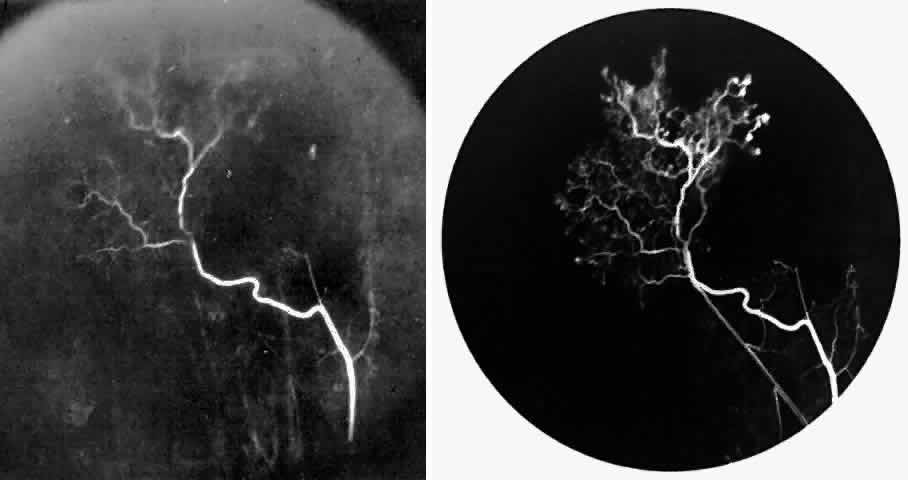

STAGE I: PERIPHERAL ARTERIOLAR OCCLUSIONS. This stage may be further subdivided into three grades: grade I, narrowing of the peripheral arterioles with tortuosity and abnormal looping of the peripheral venules; grade II, tortuosity, dilation, and microaneurysmal formation in the capillary network; and grade III, occlusion of the peripheral capillaries and arterioles.83

Histologic and trypsin digest studies support the theory of a sudden occlusion of the precapillary arteriolar circulation followed by degeneration of the occluded vessels and the distal nonperfused retina. The presence of focal areas of small vessel degeneration and vascular beading (but not typical retinal microaneurysms) also have been confirmed.132

The occluded arterioles may be invisible or may have a “silver-wire” or chalk-white appearance, as first described by Goodman and colleagues39 (Fig. 21). Fluorescein angiography may demonstrate an abrupt complete occlusion at the interface between peripheral nonperfused and posterior perfused retina. Frequently, this occlusion will take place just distal to a branching vessel, giving the appearance of a freshly pruned rose bush. The nonperfused anterior peripheral retina will have a grayish brown appearance and on fluorescein angiography will appear blurred without clearly defined fundus markings.

Fig. 21. A. Photograph of the peripheral retinal vasculature shows sheathed vessels and absence of peripheral vascular perfusion. B. Fluorescein angiogram shows area of nonperfusion representing stage I sickle cell retinopathy. White arrow points to corresponding vascular bifurcation in A and B.

STAGE II: PERIPHERAL ARTERIOLAR-VENULAR ANASTOMOSES. Following occlusion of the terminal arterioles, anastomotic channels form to channel the blood from the occluded arteriole to the nearest venules. These anastomoses form at the interface between the perfused and nonperfused retina. Most likely, they are dilated preexisting capillaries rather than new vessels, since they do not leak on fluorescein angiography. The redirection of blood flow is probably due to hydrostatic forces (Figs. 22 and 23).

Fig. 22. A. Photograph of the peripheral retina, demonstrating capillary occlusions and exudate at the margin of perfused retina. B. Fluorescein angiogram of irregular capillary border, with capillary stumps extending into nonperfused retina and an arteriolar-venular anastomosis demonstrating stage II retinopathy.

Fig. 23. Fluorescein angiogram of continuous arteriolar-venular anastomosis demonstrating stage II retinopathy. (Note that this is the same eye demonstrating the qualitatively abnormal peripheral capillary border in Figure 25.)